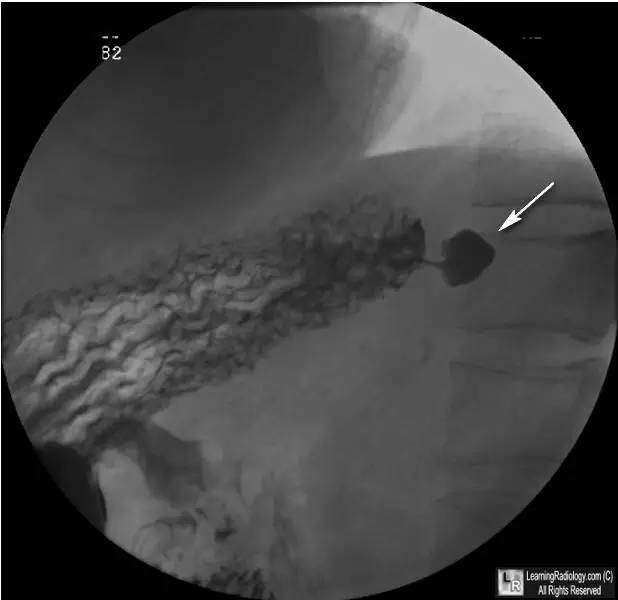

上消化道检查胃侧位观

上消化道气钡双重造影贲门部可见一外突性含钡影(白箭头),代表了胃憩室的典型部位及影像学表现。

(1)边缘清楚的半球形外突性含钡或含气影,患者站立位时可见气液平面

(2)典型者大小约1-3cm